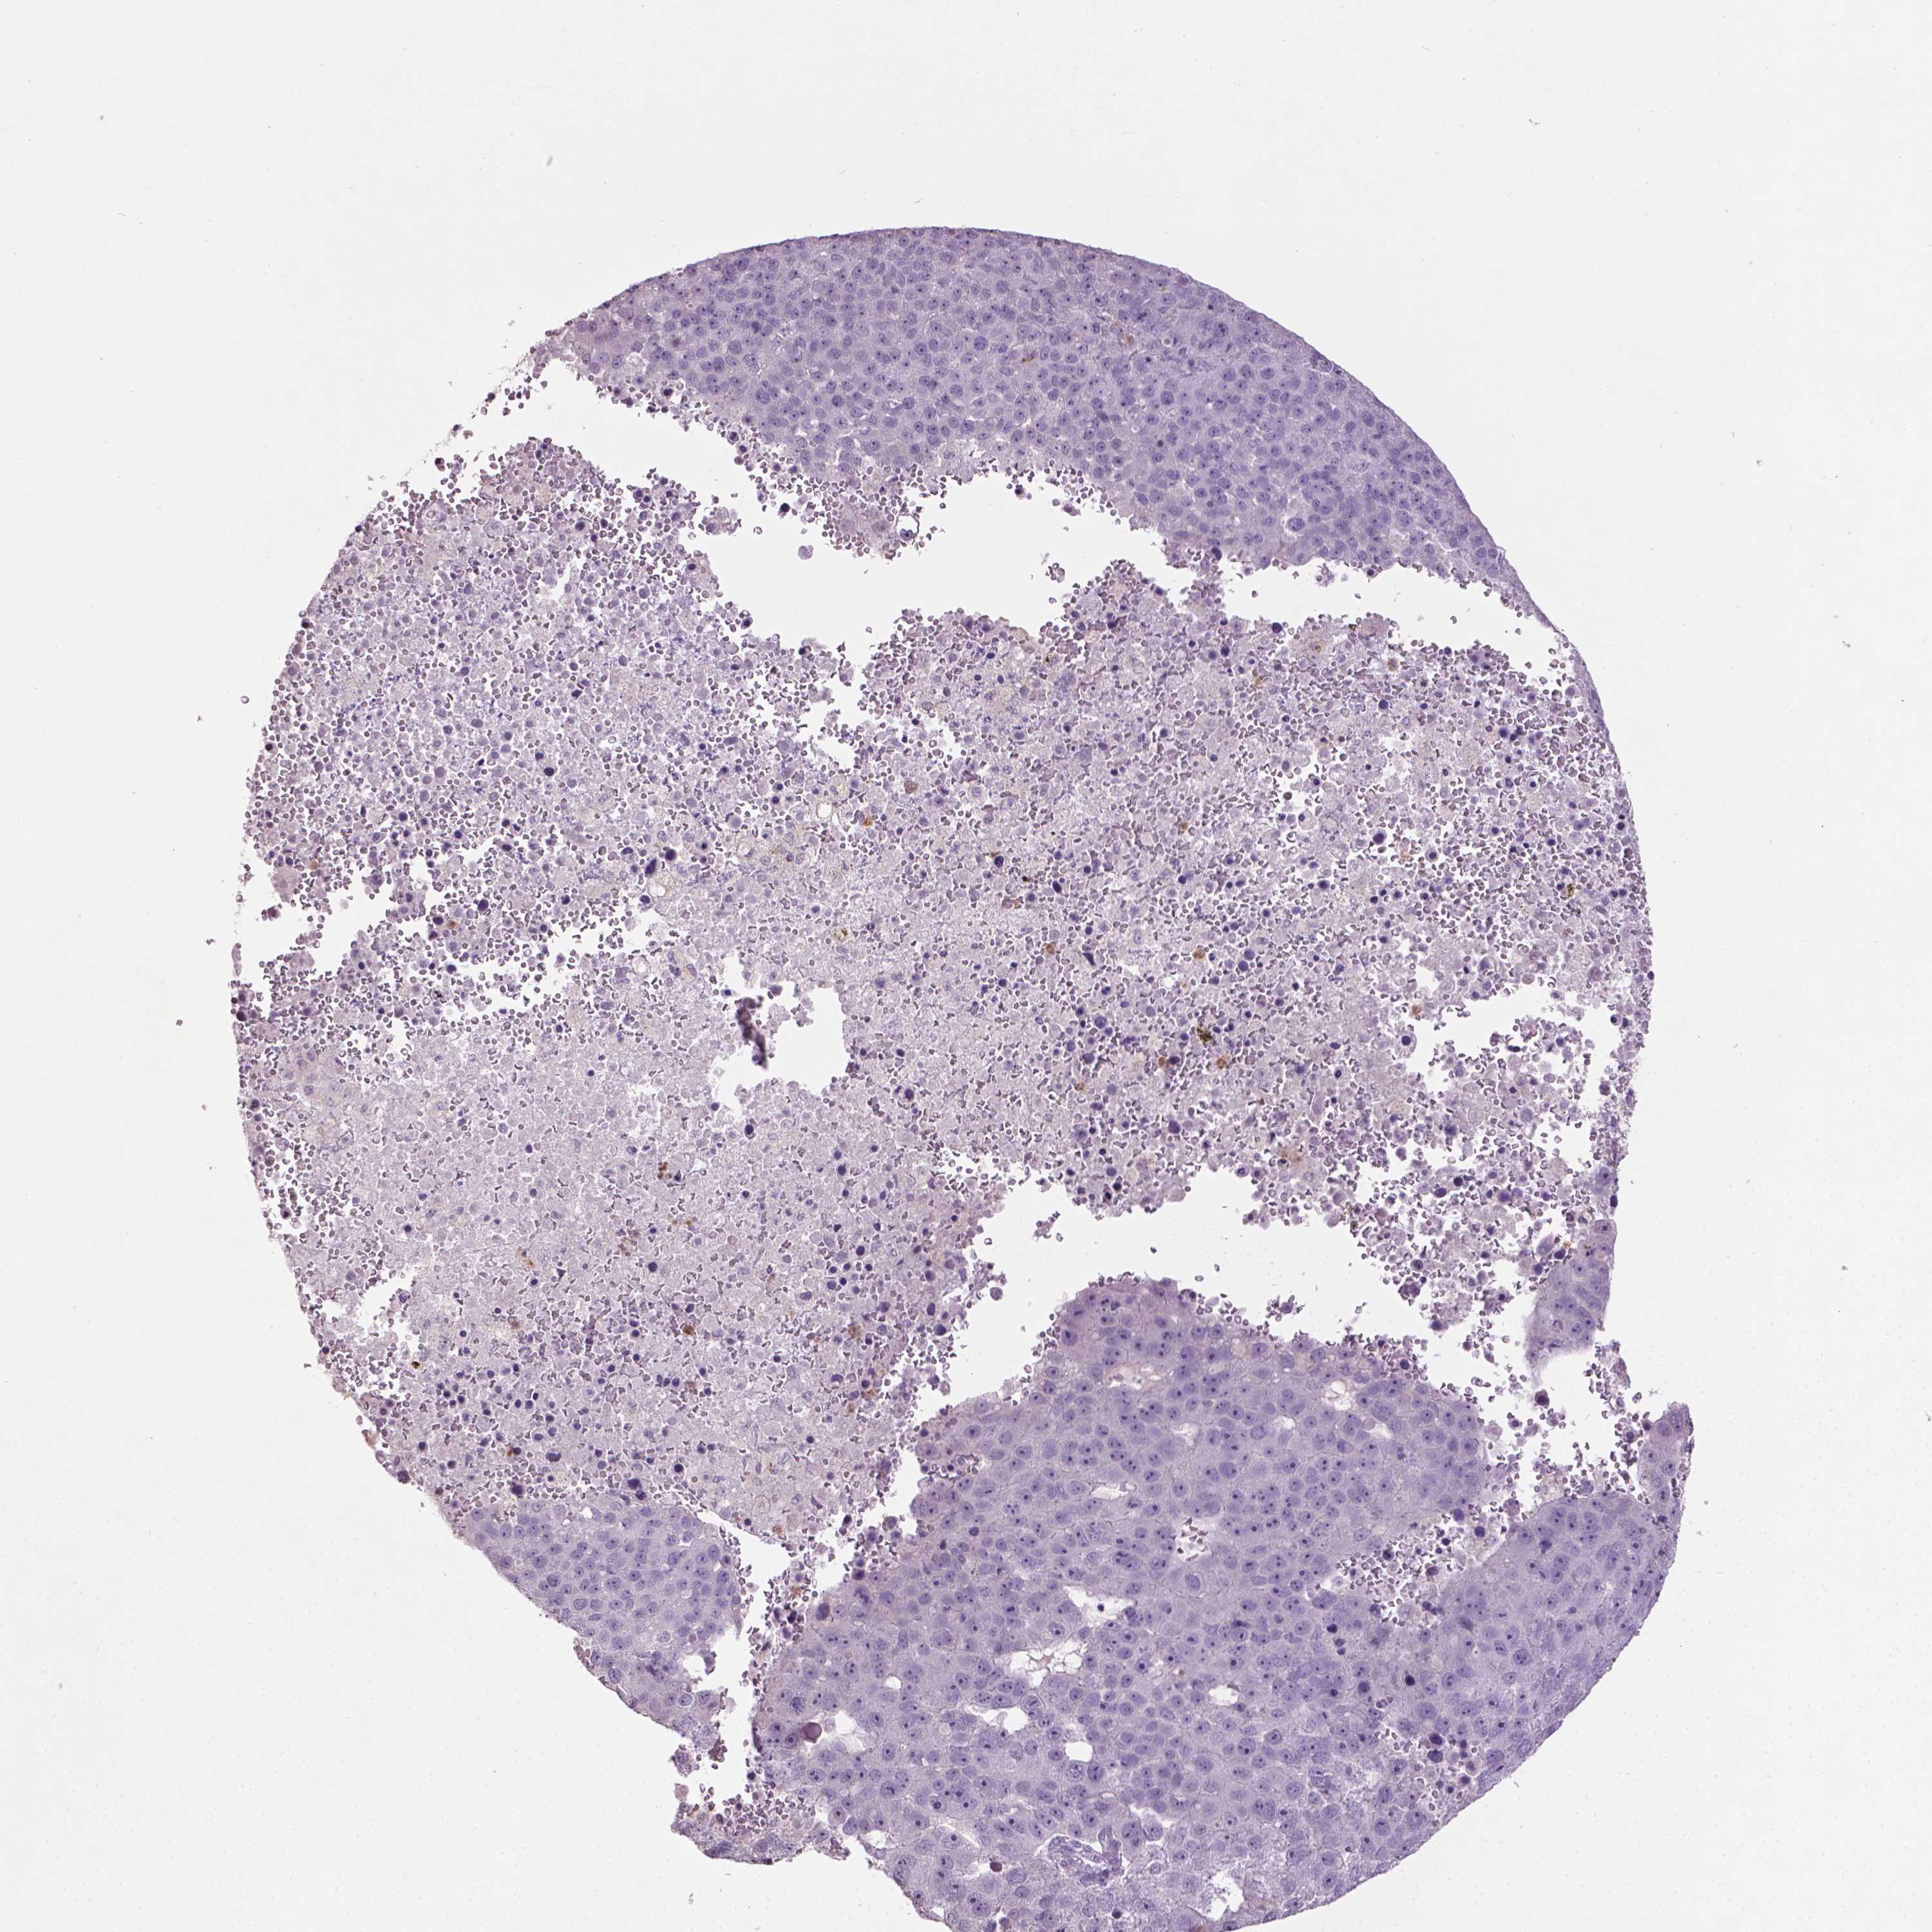

PANCREATIC CANCER - Protein expressioni

A mouse-over function shows sample information and annotation data. Click on an image to view it in a full screen mode. Samples can be filtered based on level of antibody staining by selecting one or several of the following categories: high, medium, low and not detected. The assay and annotation is described here.

Note that samples used for immunohistochemistry by the Human Protein Atlas do not correspond to samples in the TCGA dataset.

Antibody stainingi

Antibody staining in the annotated cell types in the current human tissue is reported as not detected, low, medium, or high, based on conventional immunohistochemistry profiling in selected tissues. This score is based on the combination of the staining intensity and fraction of stained cells.

Each image is clickable and will lead to virtual microscopy that enables deeper exploration of all samples and also displays staining intensity scores, fraction scores and subcellular localization as well as patient and tissue information for each sample.

Antibody HPA071290

Staining

High

Medium

Low

Not detected

Intensity

Strong

Moderate

Weak

Negative

Quantity

>75%

75%-25%

<25%

None

Location

Nuclear

Cytoplasmic/membranous

Cytoplasmic/membranous,nuclear

Adenocarcinoma, NOS